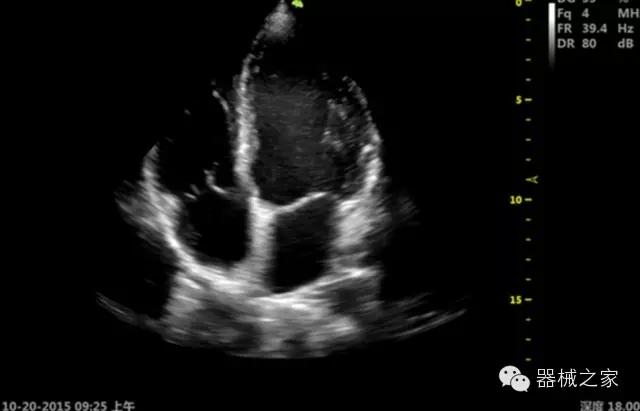

臨床圖片賞析

·飛依諾特有心臟純凈波探頭提供更好的穿透力和彩色敏感度,以及結(jié)合TView梯形拓展改善困難病人深部組織成像;